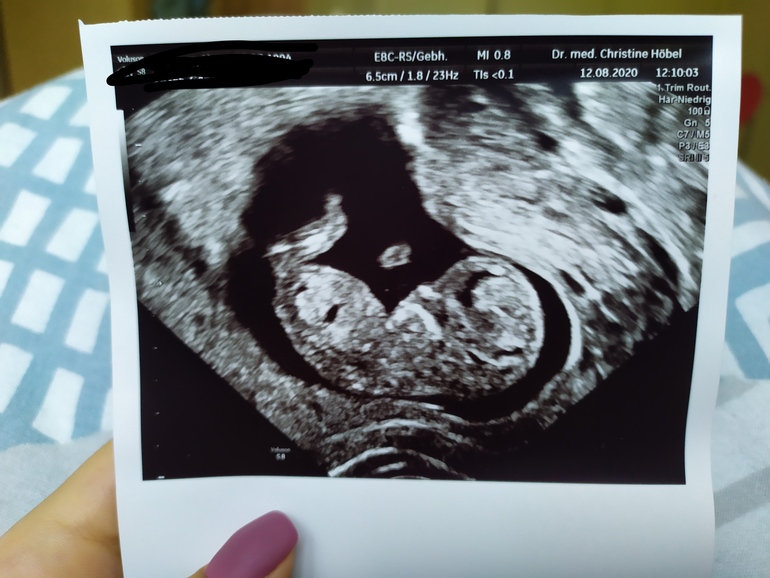

Первый скрининг - done✔️

Пол малышаДобрый день ББ)) сегодня я прошла свой первый скрининг,слава Богу вроде всё в порядке, ТТТ! Тут конечно такой скрининг, НЕДОскрининг... Срок 11+4.

Вопрос к вам девочки, кто что скажет по поводу пола малыша? Мне кажется на этих фото половой бугорок не попал "в кадр", но может вдруг кто разглядит🤪 в Германии пол до 14 недель не говорят😔 для меня это в общем-то не особо важно, хотелось бы девочку конечно, но если мальчик тоже не расстроюсь. Вроде🤭 муж зато наоборот хочет пацана. Ну короч стандартная ситуация 🤦😆 мне главное чтоб ребёнок здоровый родился и желательно под счастливой звездой как говорится 🙈😄

УЗИ, кстати, делали вагинально, я хз почему. Ещё и щупала матку какого-то Х! Мужу рассказывала и показывала на фото чем делают трансвагинально УЗИ, но чёт он по-моему всё равно немножко в шоке был😆 И да, мужа впустили вообще без проблем (к слову о карантине).

Малышок сначала походу дрых, а потом как забацал сальто и перевернулся на другую сторону)) так мило))) думала буду реветь, неее, лежала как мумия в монитор таращилась с покер фэйс😆 а вот когда уже фото дома начала рассматривать так сидела лыбилась как дура🥴😄😍